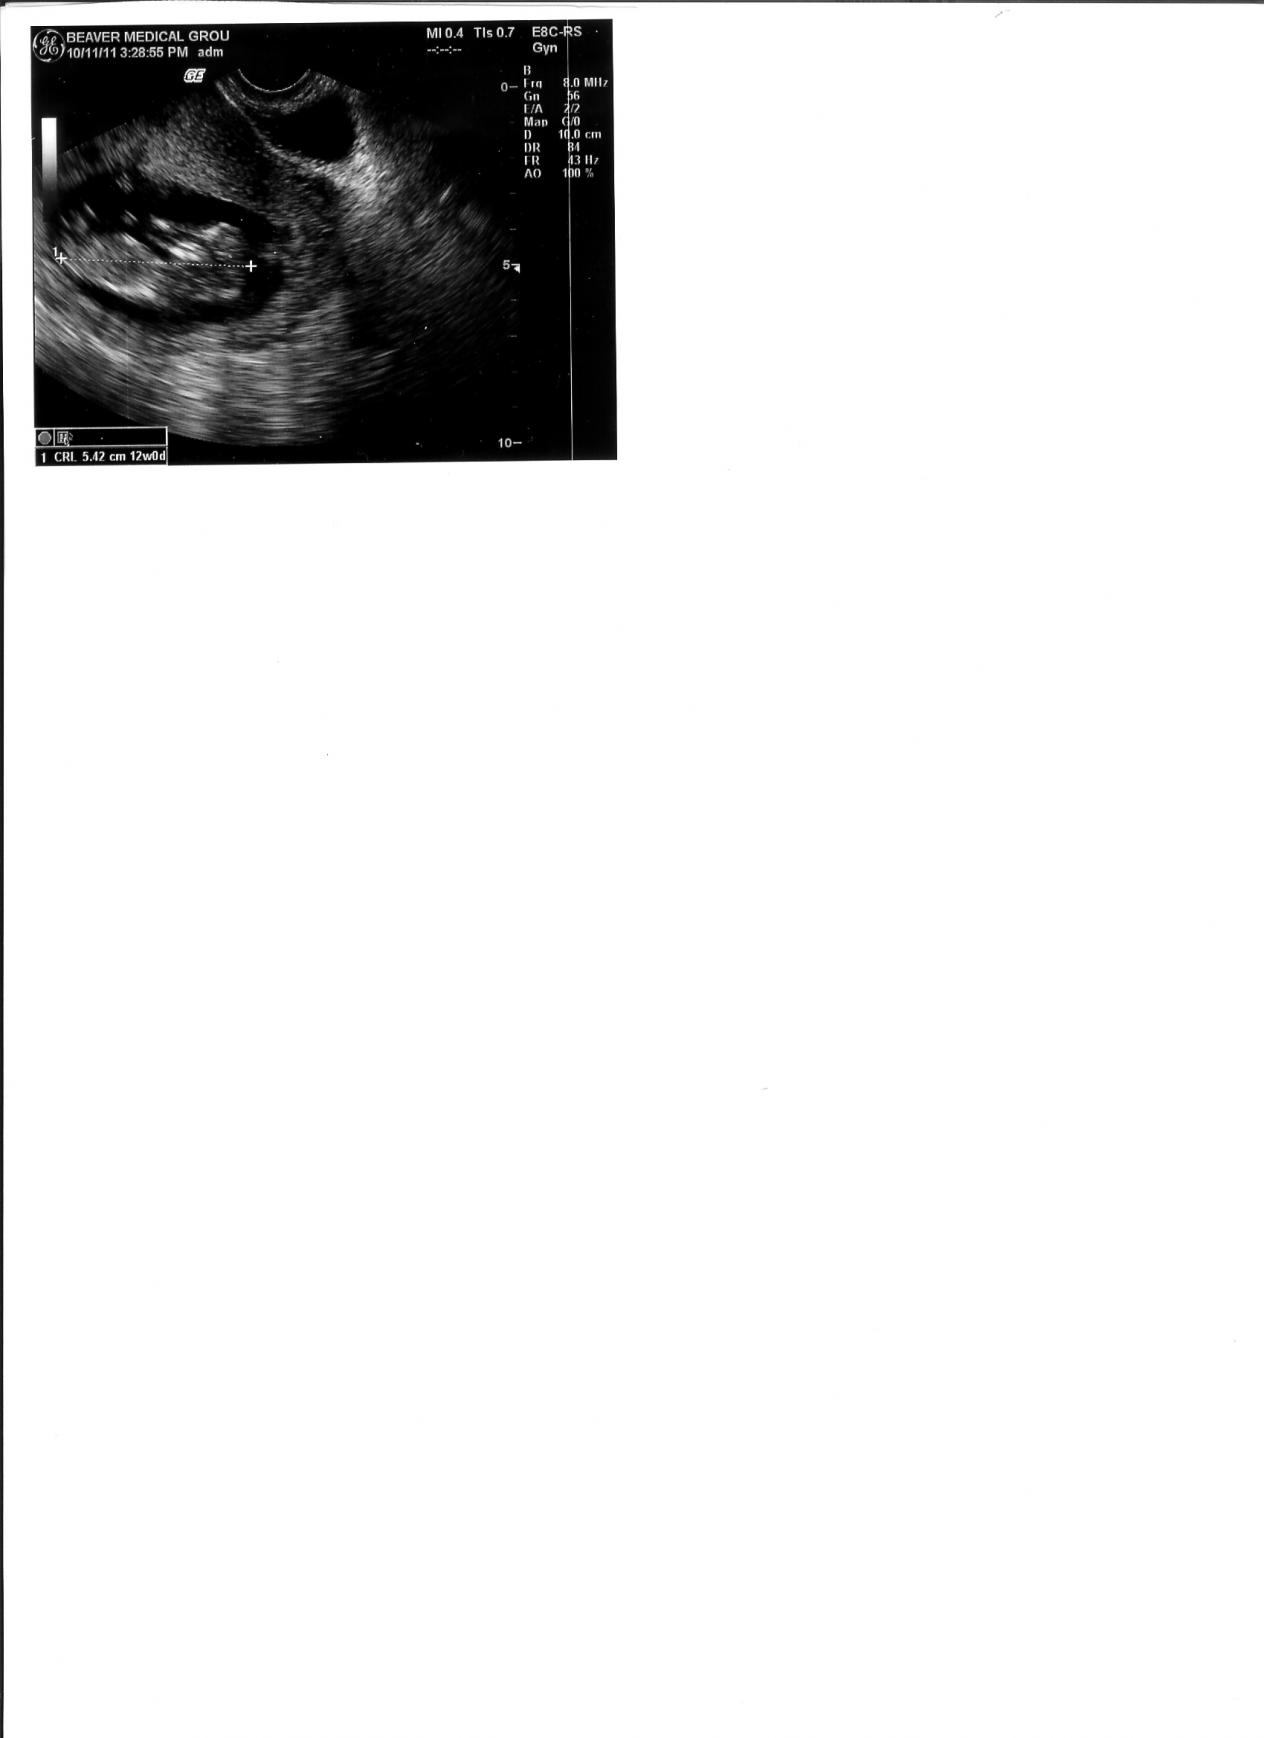

I know this is not a very good picture, but are there any gender clues? It is 12 weeks.

Leaning girl.

Not a great image to guess on. 50-50 from me.

This pic is so busy down there I can't tell sorry.GL!